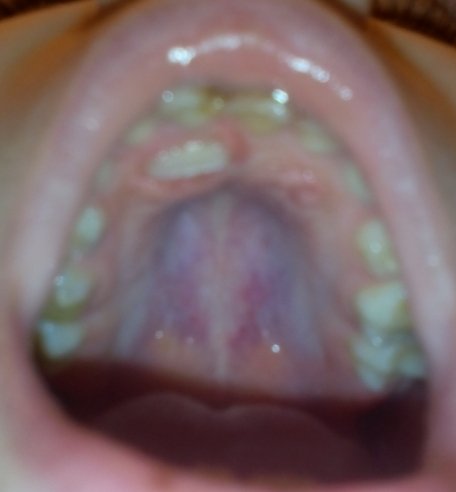

Девочка 7 лет, неправильно растет 2 или 3 верхний зуб ( не из того места), что необходимо делать?